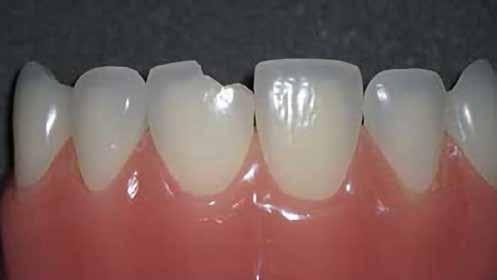

A betétek készítéséről készülök előadást tartani. Ez a terület hallgató korom óta tetszett, és mára a rendelőnkben végzett kezelések jelentős részét teszi ki.Héjkerámiák ragasztására váró fogak.

Egy teljes mosoly megtervezésekor vagy javításakor – akár közvetlenül, akár közvetve – a klinikus vagy a technikus alkotó, akinek feladata egy művészi remekmű létrehozása. Egy metszőfogtörés esetében azonban a klinikus kevésbé alkotó, mint inkább kovácsmester, akinek a környező és szomszédos fogazat minden optikai szempontját le kell utánoznia. Ez kihívást jelenthet az árnyalatválasztás szempontjából, mivel a legnagyobb színvariabilitás jellemzően a metszőfogak metsző harmadában található. Ez különösen igaz a fiatalabb páciensekre, akiknek gyakran van kiemelkedő áttetszőségük és opacitásuk ebben a régióban.